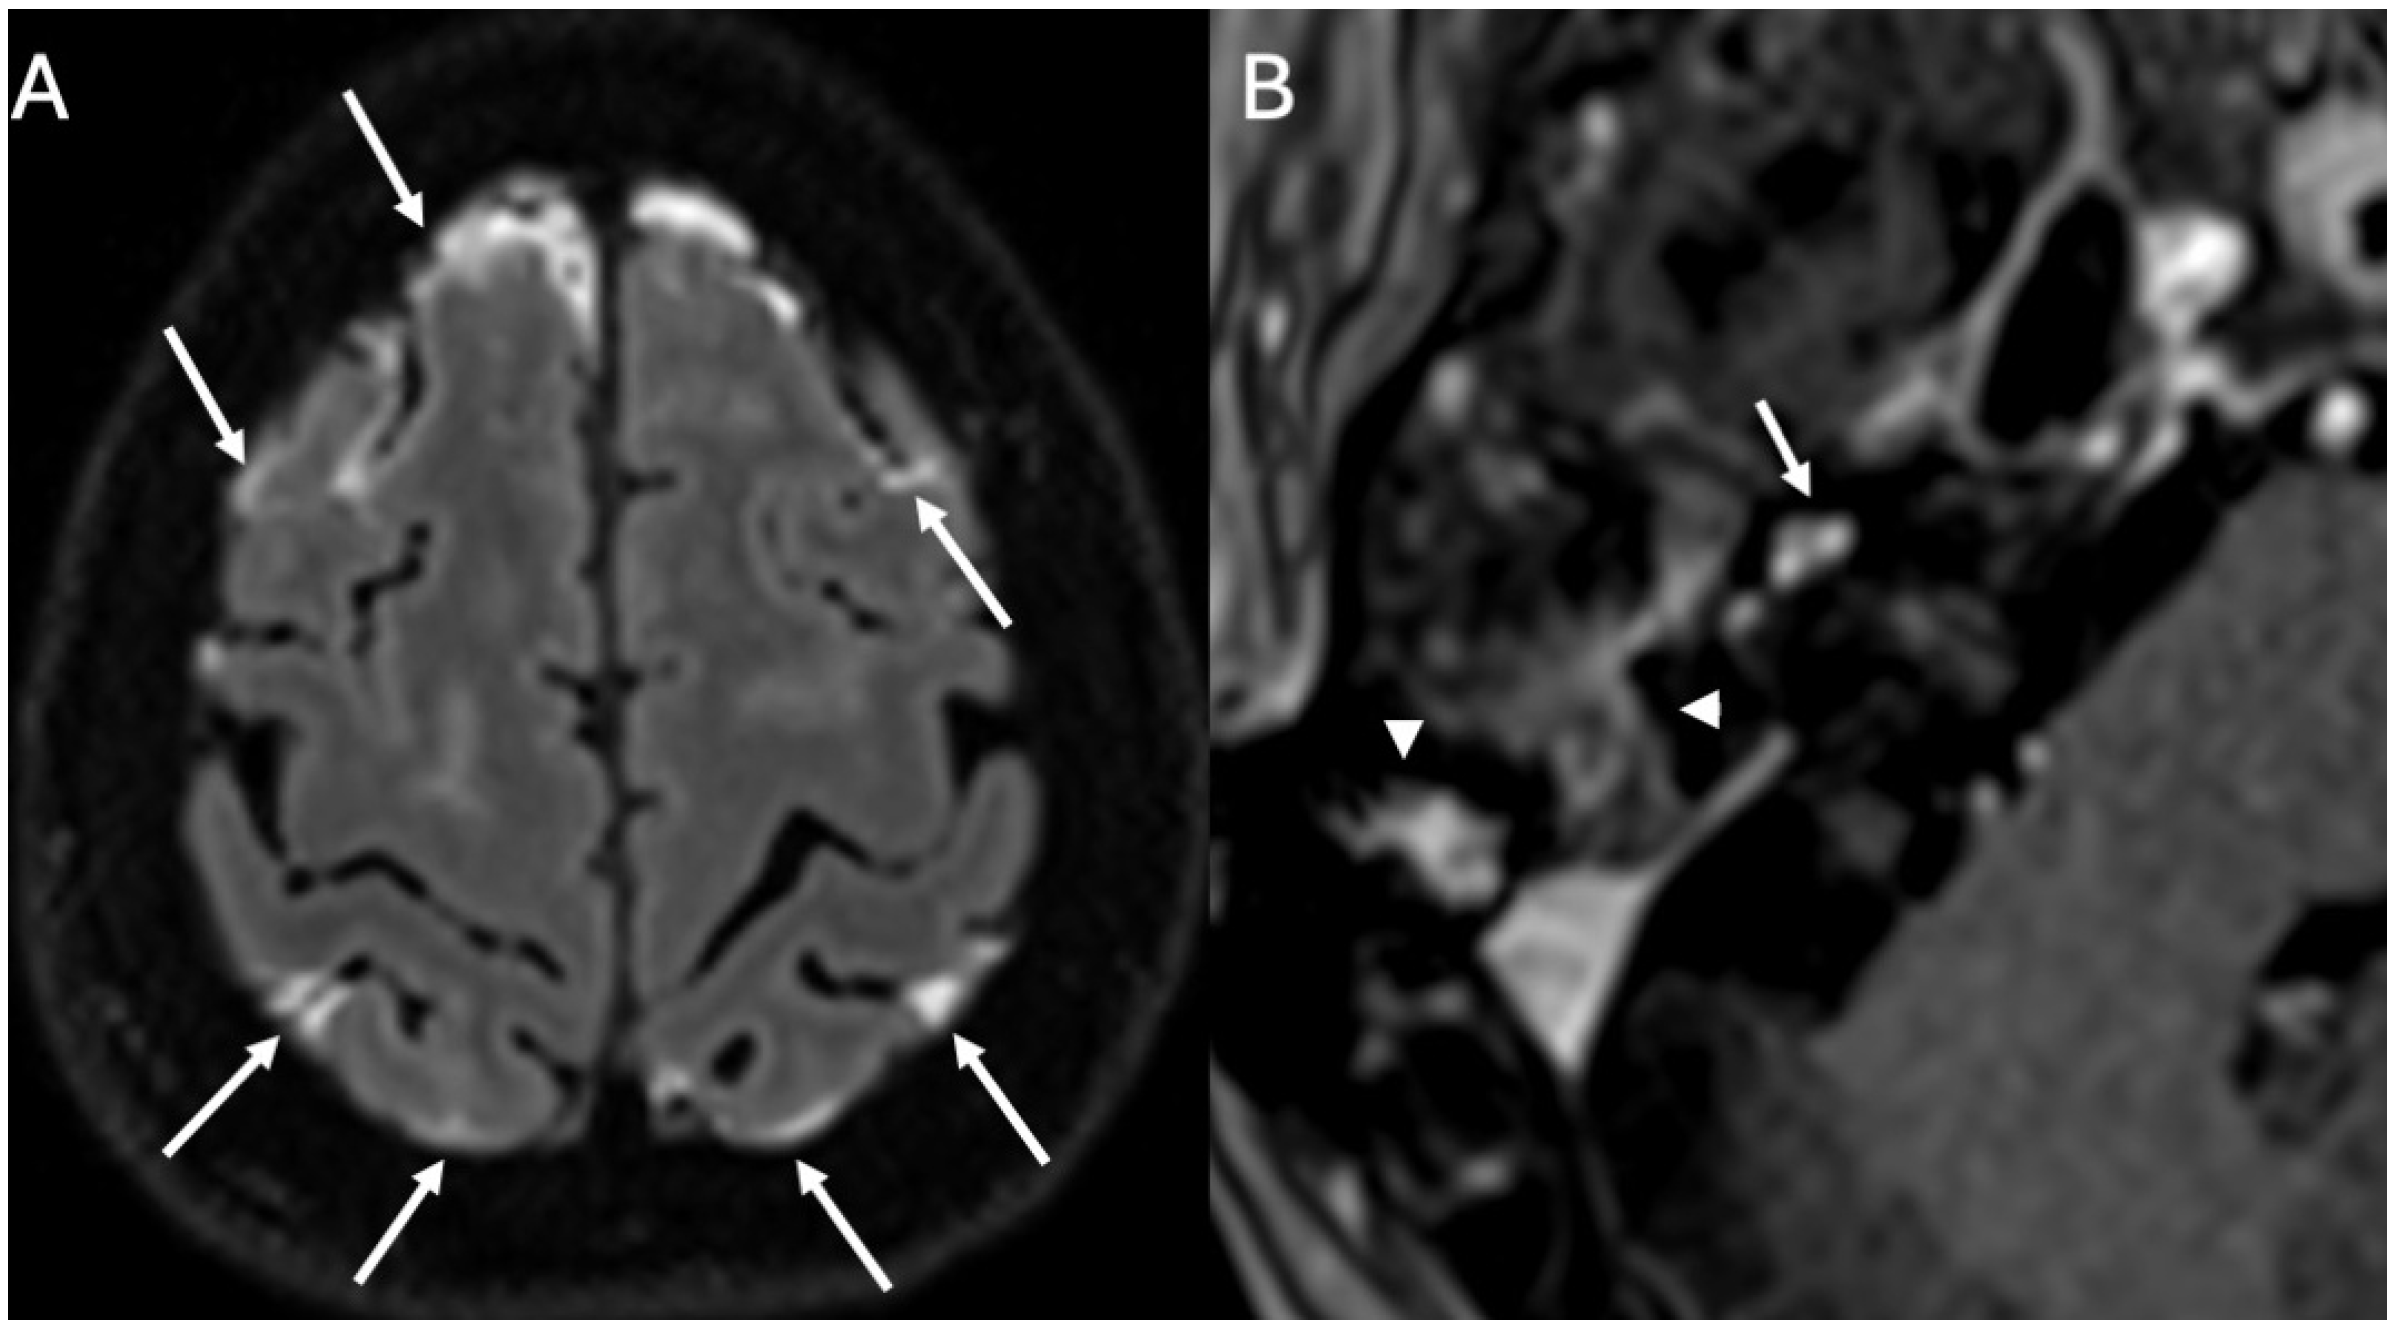

3.1. Otomastoiditis

3.1.1. Imaging